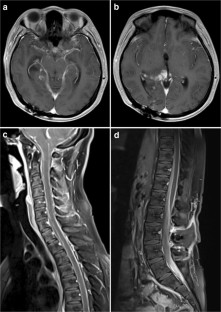

A 15-year-old girl after 1 week of symptoms was found to have a T2/FLAIR-hyperintense and contrast-enhancing thalamic mass accompanied by leptomeningeal enhancement along the entire neuraxis. Initial infectious workup was negative, and intracranial biopsy was inconclusive. Spinal arachnoid biopsy revealed an H3K27M-mutant lesion with glioneuronal features, classified thereafter as DMG. She received craniospinal irradiation with a boost to the thalamic lesion. Imaging 1-month post-radiation demonstrated significant treatment response with residual enhancement at the conus.